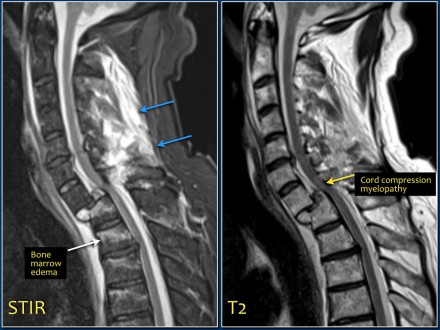

The images are of a patient with a typical bamboo spine as a result of ankylosing spondylitis.

After a fall on his back no fracture was seen on the x-rays.

However the CT shows a thin fracture line through the anterior side of the vertebral body and also through the spinous process.

Continue with the MR-images.

Look at the images.

What are the findings?

Then scroll to the next images.

The findings are:

- Vertebral bodies show marrow edema as a result of a fracture.

- Torn flaval ligament (yellow arrow).

- Fractures through the posterior elements (red arrows).

The TLICS-score is high, because there is distraction and injury to the PLC.